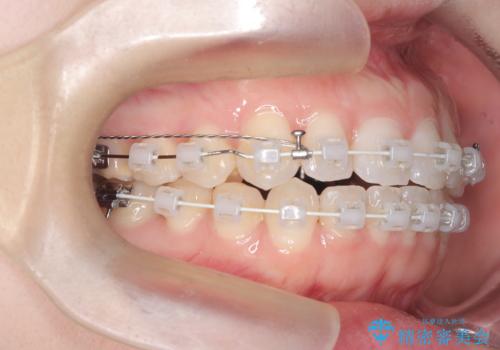

審美ワイヤー矯正とTAD併用による犬歯の遠心移動

- 歯並びの乱れを改善したいと来院されました。精密検査の結果、犬歯を奥へ動かすことで、より美しい口元と安定した咬み合わせが得られると診断。患者様のご希望から、目立ちにくい審美ワイヤー矯正を採用し、効率的な歯の移動のために**リンガルアーチとTAD(矯正用アンカースクリュー)**を併用する計画を立てました。これにより、抜歯せずにスペースを確保し、犬歯をスムーズに遠心へ移動させます。

今回の矯正では、装置が目立たないよう透明なブラケットと白いワイヤーを使用。さらに、効率的な歯の移動のために、歯の裏側にリンガルアーチを設置しました。また、確実な奥歯の移動のために**TAD(矯正用アンカースクリュー)**を一時的に使用。これにより、犬歯を狙った位置へ正確に動かすことが可能に。目立ちにくい装置で快適に過ごしながら、理想的な歯並びと咬み合わせを獲得していただけました。